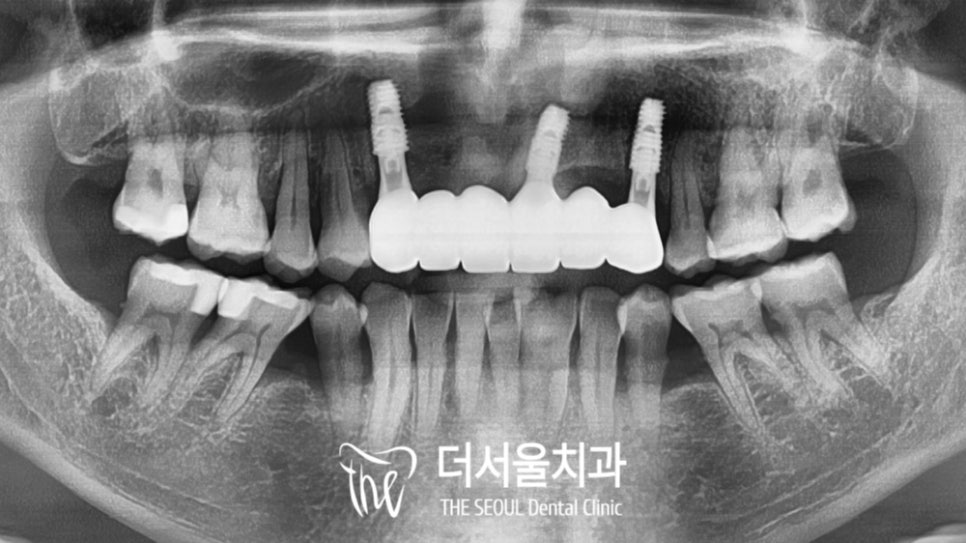

약 3개월 뒤 완성된 브릿지를

세팅한 모습입니다.

튼튼하게 제작되어 자리를 잡고 있는데요.

훨씬 건강하게 바뀐 것을 볼 수 있네요.

융합치 등을 고려하여 만들었더니

앞니 교합 또한 잘 제작되어

걸리는 곳 없이 편하게 물린다고 말씀을 하셨습니다.